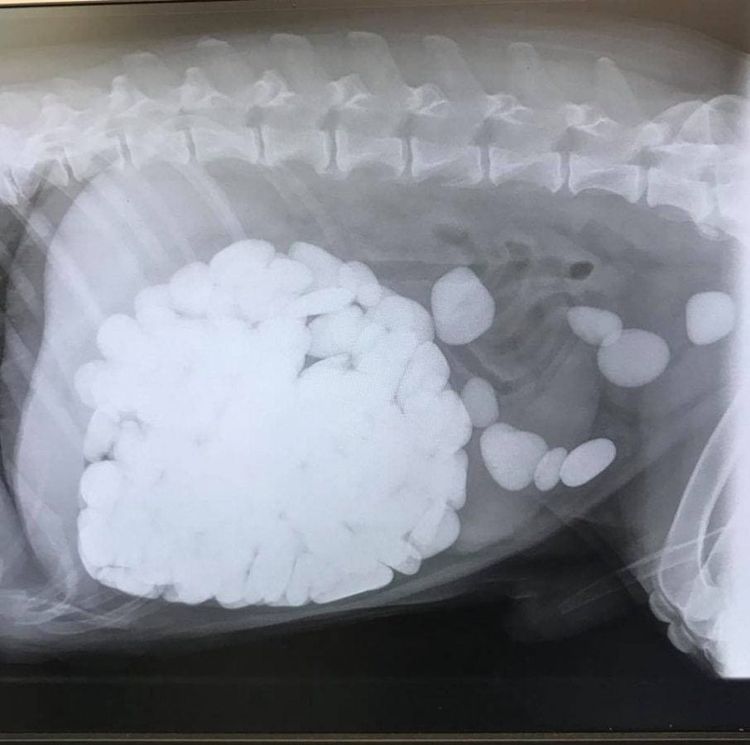

After undergoing an X-ray, the vets and owners were amazed to see Dilyn’s stomach was completely full of stones, which the vets believe was something “unlikely to have been seen by any vet in the UK”.

Vet Amy O’Regan spent nearly three hours painstakingly removing each and every pebble, counting an incredible 206 in total during surgery.

“We really thought the worst when we saw the X-ray – how are we going to get all these out?